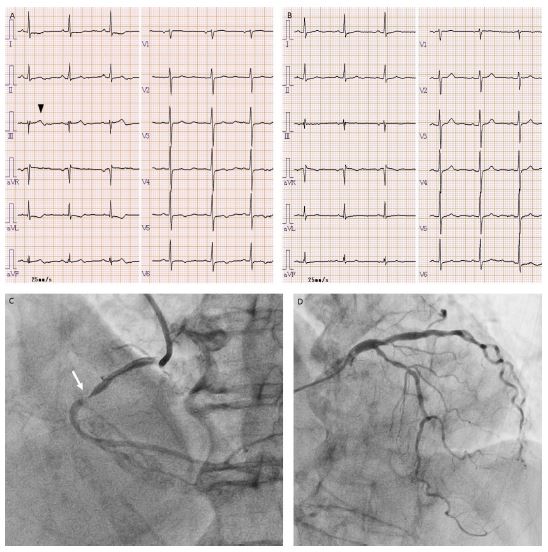

Electrocardiography revealed slight ST-segment elevation, along with terminal T-wave inversion, in the inferior leads, and minimal ST-T changes in the lateral leads (A), compared with the findings from four months earlier (B). Chest radiography and echocardiography were unremarkable. The high-sensitivity troponin T level was 0.165 ng/mL (reference value: ≤0.014), and the creatine kinase level was 88 U/L (reference range: 41 to 153). A diagnosis of acute coronary syndrome was made, and emergency coronary angiography revealed semi-occlusion in the middle portion of the right coronary artery (C, arrow) with no collateral flow from the left coronary arteries (D). Subsequent coronary intervention with stent implantation was successfully performed, and her postoperative course was uneventful, with no creatine kinase elevation above the upper limit of normal.

Figure 1: Electrocardiography and coronary angiography.

Electrocardiography at presentation (A) shows slight ST-segment elevation and terminal T-wave inversion in the inferior lead, typically in lead III (arrowhead), along with ST-T segment abnormalities in the lateral leads. None of these abnormalities were present in the findings from four months earlier (B). Emergency coronary angiography reveals semi-occlusion in the middle portion of the right coronary artery (C, arrow) and mild to moderate stenoses in the left anterior descending and left circumflex arteries, with no collateral flow to the distal portion of the right coronary artery (D).